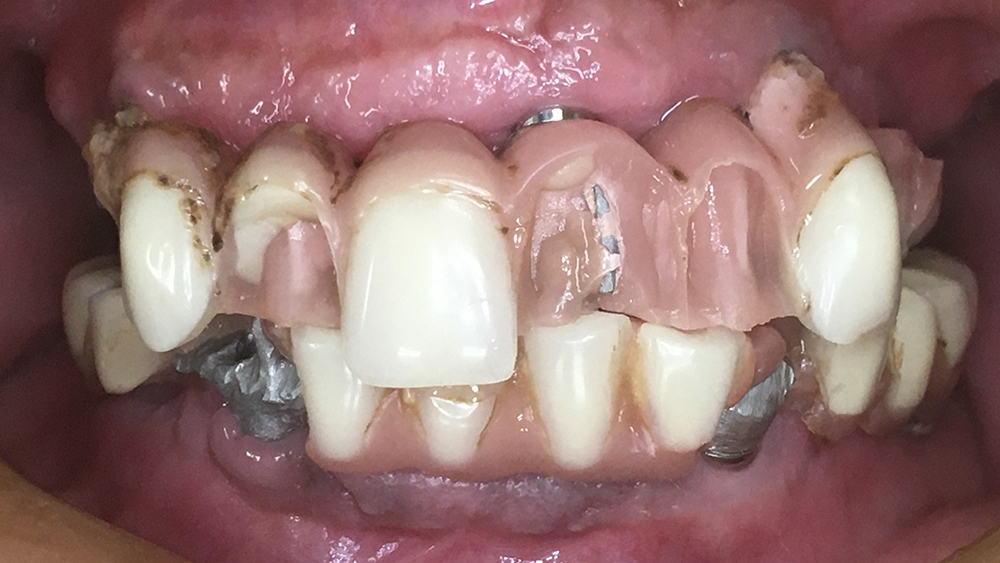

症例2

Before

After

WYさん 60代女性

非喫煙者、重度歯周病

治療の期間・回数:一度目:上下とも約6か月/オールオン4:5か月

​治療の価格:一度目:上の歯1,600,000円、下の歯700,000円

オールオン4:1,600,000円

治療内容:この方は40代で重度の歯周病になり、多くの歯を失いました。

20年前に、上あごには4本のインプラントを入れましたが、骨が少なかったため、手術中に骨が割れるトラブルがありました。そのため、4か月間待ってから仮の歯を入れました。

下あごは残っている歯を使ってブリッジを作りました。最終的には上下とも、金属の土台にセラミックを貼った「メタルボンド」の歯を入れています。

その後、下あごのブリッジは10年も持ちましたが、最終的には全ての歯を失いました。そこで韓国製オステムのインプラントで「オールオン4」という方法で再建しました。手術当日に仮の歯を入れ、最終的にはスクリューで固定するメタルボンドの歯を入れています。

重度の歯周病で骨も少ない条件でしたが、上あごのインプラントは19年間安定して使えています。